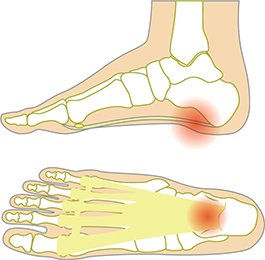

플랜타르 패시아염 (족저근막염)

- 발바닥의 아치에 위치한 두꺼운 섬유 조직인 족저근막이 염증이 생기는 질환입니다. 주로 장시간 서 있거나 걷는 경우, 혹은 비만으로 인해 과도한 압력이 가해져 발생합니다. 통증은 주로 아침에 일어났을 때 첫 발을 내딛을 때 가장 심하게 느껴지며, 점차 운동 후에도 나타날 수 있습니다.